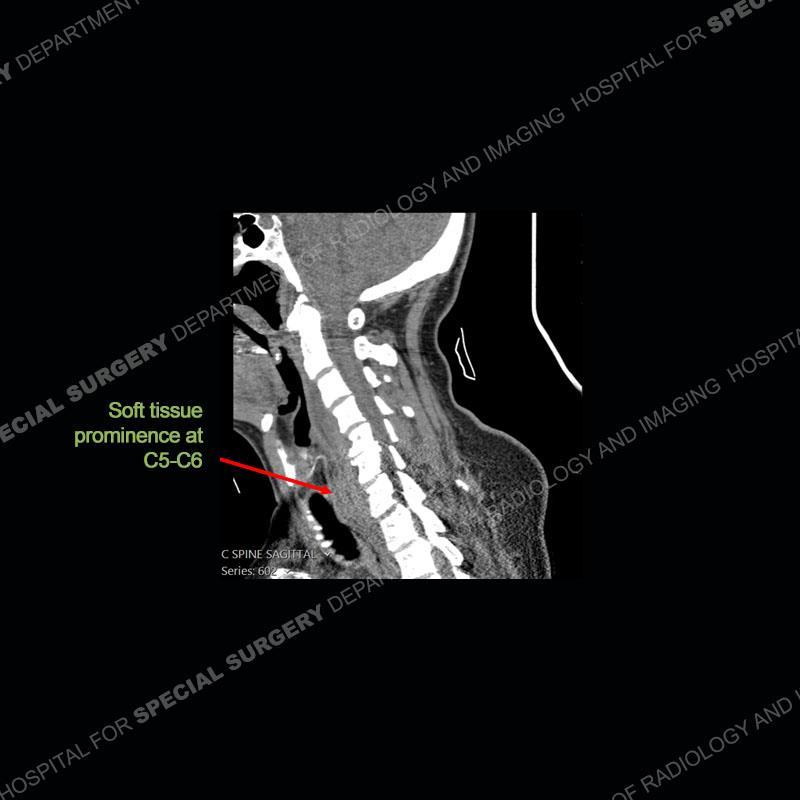

The radiographs demonstrate a prevertebral soft tissue fullness centered at C5-C6 that persists even on extension. There is a slight loss of disc height at C5-C6. The CT more readily shows the prevertebral soft tissue swelling at C5C6 where there is a punctate focus of gas. On the MRI, there is a marked amount of edema and a heterogeneous collection in the prevertebral soft tissue at C5-C6. Edema is present of the C5 and C6 vertebral bodies with a loss of the normal architecture about the disc space. A heterogeneous epidural collection has formed that causes compression of the spinal cord asymmetric to the left side and also precipitates severe left sided neural foraminal stenosis.